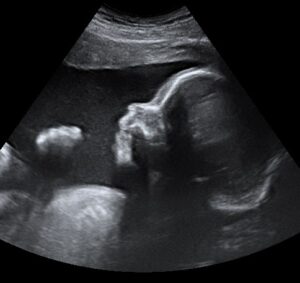

La ecografía 4D es mucho más que una imagen en movimiento: es una oportunidad única para conocer al bebé antes de su nacimiento y, al mismo tiempo, una herramienta médica avanzada que permite observar su desarrollo con gran precisión.

Gracias a la tecnología de alta resolución, podrás ver sus rasgos, sus movimientos e incluso sus gestos, viviendo una experiencia emocionante y cercana. Para el equipo médico, esta técnica ofrece una valiosa información sobre el bienestar fetal, la posición y el crecimiento del bebé, siempre con total seguridad para la madre y el futuro recién nacido.

Recomendamos realizar la ecografía 4D entre las semanas 26 y 32 de embarazo, el momento ideal para obtener las mejores imágenes.